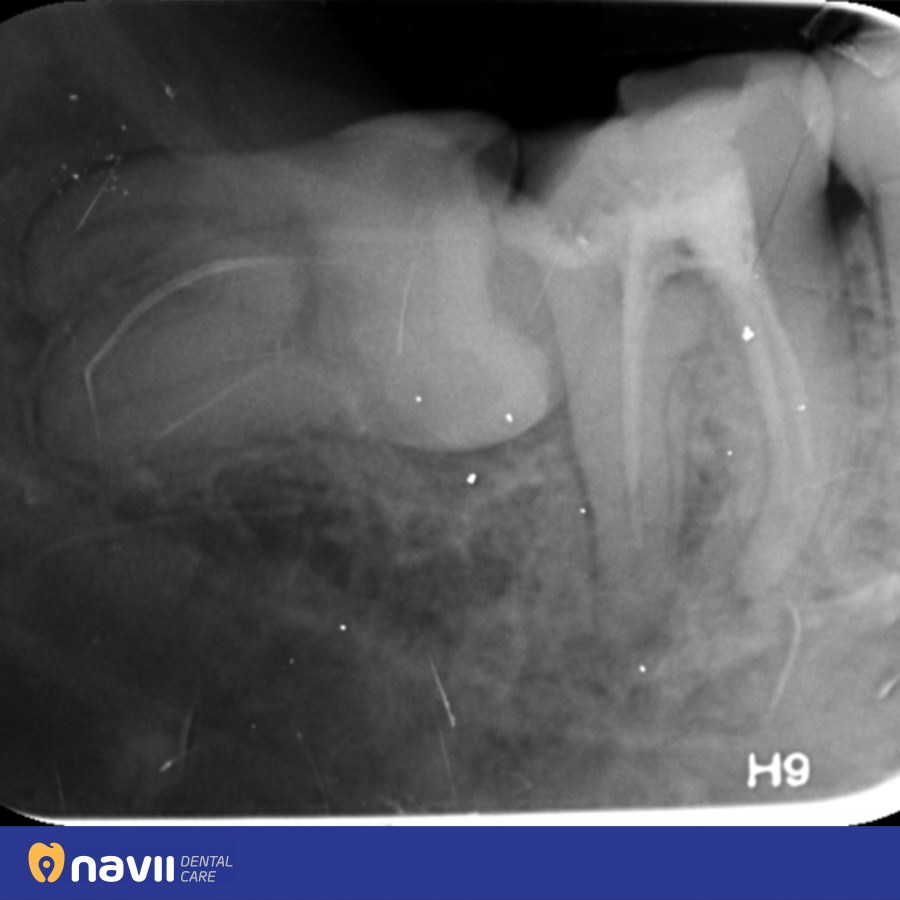

Răng khôn mọc khi xương hàm đã ổn định và vững chắc, trên cung hàm chật hẹp thường chỉ đủ chỗ cho 28 răng vĩnh viễn. Vì vậy, răng khôn thường mọc ở các tư thế không thuận lợi như: mọc ngầm, mọc lệch, mọc đâm ngang, mọc thẳng nhưng dị dạng,…

Đa phần các trường hợp răng khôn sẽ đâm vào răng số 7 gây sâu răng số 7. Trên thực tế, đã có rất nhiều Bệnh nhân đến khám tại DDS và mất răng số 7 bắt nguồn từ chiếc răng khôn này.